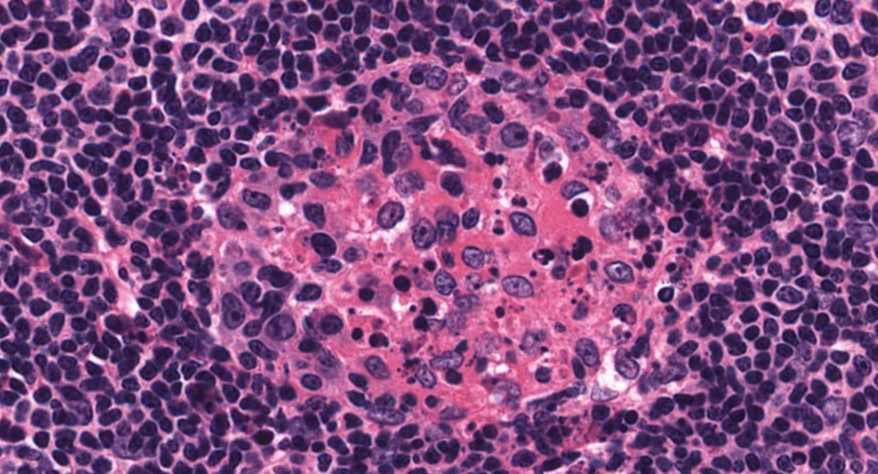

低倍镜:胸腺表面包有薄层结缔组织构成的被膜,结缔组织深入实质,将胸腺分成许多不完整的小叶。每个小叶分为周围的皮质和中央的髓质两部分。皮质中胸腺细胞排列密集,故染色深;髓质中胸腺细胞较少,胸腺上皮细胞多,故染色浅,其中可见染成红色的圆形小体-胸腺小体。高倍镜:胸腺小体大小不等,由几层至十几层扁平的胸腺上皮细胞呈同心圆状排列而成,其外周的细胞较幼稚,细胞核明显;小体中央部分的上皮细胞已退化,细胞核消失,胞质呈均质状,染成红色。

7.胸腺小体1

8.胸腺小体2